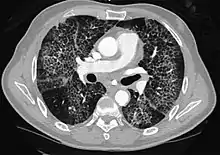

- Lung adenocarcinomaCT image showing diffuse GGOs throughout both lungs. An abscess is also noted in the right lung (screen left).

The diffuse pattern typically refers to GGOs in multiple lobes of one or both lungs. Broadly, a diffuse pattern of GGO can be caused by displacement of air with fluid, inflammatory debris, or fibrosis. Cardiogenic pulmonary edema and ARDS are common causes of a fluid-filled lung. Diffuse alveolar hemorrhage is a rarer cause of diffuse GGO seen in some types of vasculitis, autoimmune conditions, and bleeding disorders.[6]

Inflammation and fibrosis can also cause diffuse GGOs. Pneumocystis pneumonia, an infection typically seen in immunocompromised (e.g. patients with AIDS) or immunosuppressed individuals, is a classic cause of diffuse GGOs. Many viral pneumonias and idiopathic interstitial pneumonias can also lead to a diffuse GGO pattern. Radiation pneumonitis, a side effect of pulmonary radiation therapy, can lead to pulmonary fibrosis and diffuse GGOs.[6]